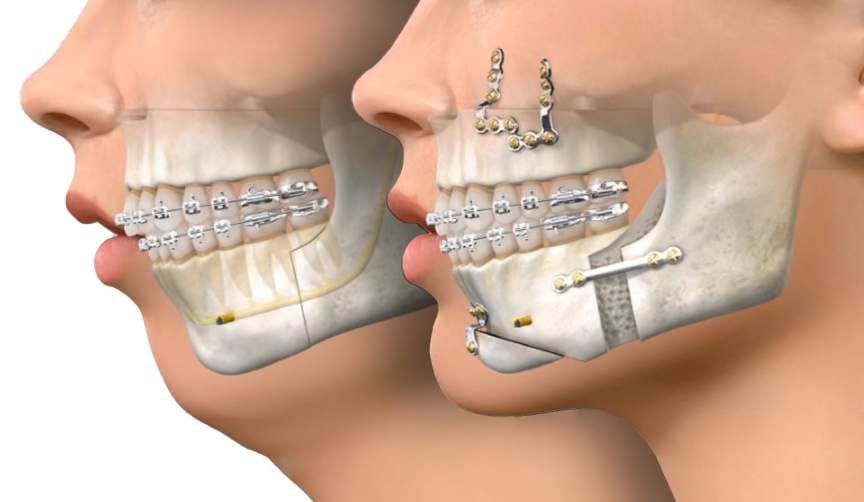

4mm downgraft in total of the lower third

4mm anterior downward custom wedge shaped genio

3 mm posterior genio

10mm ramus widening - 5mm each sided

a combo of clockwise and counter clockwise rotation to fix my canted mandible

3mm of lefort 1

Im not getting a big lefort movement. My bimax will be focused on more vertical height then forward growth. Since I’m not getting a big lefort movement should I still ask for the alar synch to avoid as much as possible any alar base expansion.